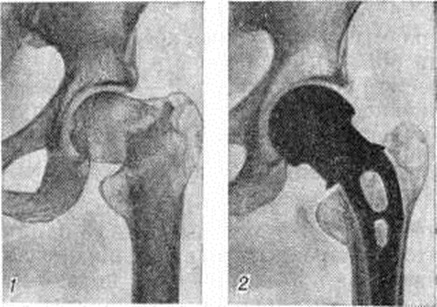

При выборе метода лечения Переломы (особенно оперативного) важно выяснить адаптационно-компенсаторные возможности и резервные силы организма. Пожилым ослабленным больным предпочтительно применять простые, легко переносимые и сравнительно безопасные приёмы лечения. Следует избегать методов лечения, вынуждающих длительно лежать в постели и затрудняющих передвижение. У данного контингента больных значительно возрастает степень операционного риска. Поэтому оперативное вмешательство по поводу Переломы у пожилых людей нужно применять тогда, когда консервативные методы не эффективны, а также в тех случаях, когда оперативный способ может быть легче перенесён больным, чем консервативный. Оперативное лечение наиболее часто применяют при аддукционных (варусных) медиальных Переломы шейки бедренной кости. В этих случаях показан остеосинтез трёхлопастным гвоздём или другим фиксатором, а также эндопротезирование (рисунок 12 и 13). При соответствующих показаниях вертельные и диафизарные Переломы бедра также лечат оперативно.

Рис. 12.

Рентгенограммы тазобедренного сустава с медиальным переломом шейки бедра: 1— до операции (видно смещение отломков), 2— прямая и 3— боковая рентгенограммы после остеосинтеза трёхлопастным гвоздём.

Рис. 13.

Прямые рентгенограммы тазобедренного сустава при переломе шейки бедра: 1— до операции; 2— после эндопротезирования головки и шейки бедра.